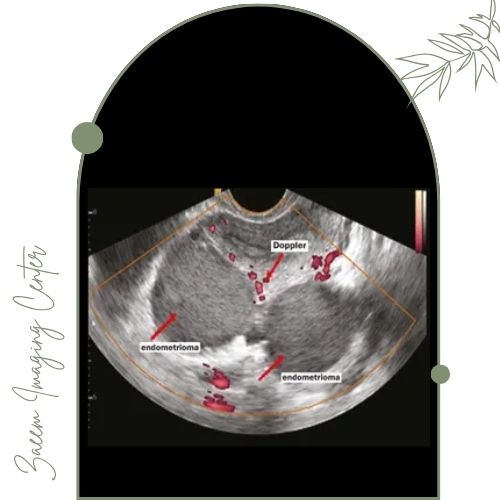

مرکز تصویربرداری پزشکی زعیم تحت مدیریت دکتر علیرضا سرزعیم (فلوشیپ مداخلهای) با همکاری دکتر سمیه زارعی و دکتر مهرناز راسته تخصصیترین خدمات ارزیابی و تشخیص اندومتریوز را ارائه میدهد. این مجموعه با به کارگیری تکنولوژی نوین امکان شناسایی ضایعات اندومتریوز، چسبندگیها و کیستهای مربوطه را بدون نیاز به روشهای تهاجمی و با بالاترین سرعت و دقت ممکن فراهم کرده است.تجهیزات پیشرفته مرکز

در این مرکز ابزارهای تصویربرداری مدرن و استانداردهای بهروز جهانی مورد استفاده قرار میگیرند. دستگاههای نسل جدید با بهرهگیری از فناوری تصویربرداری تخصصی اطلاعات مورد نیاز را فقط در چند دقیقه جمعآوری کرده و همه اطلاعات در کنار تفسیر تخصصی تیم پزشکی در کوتاهترین زمان در اختیار شما قرار میگیرد. همچنین بیماران میتوانند برای پیگیری روند بیماری، بررسی تأثیر درمان یا غربالگری مشکلات زمینهای از خدمات دقیق و قابل اطمینان همواره بهرهمند شوند.مزایای خدمات سونوگرافی اندومتریوز در مرکز زعیم